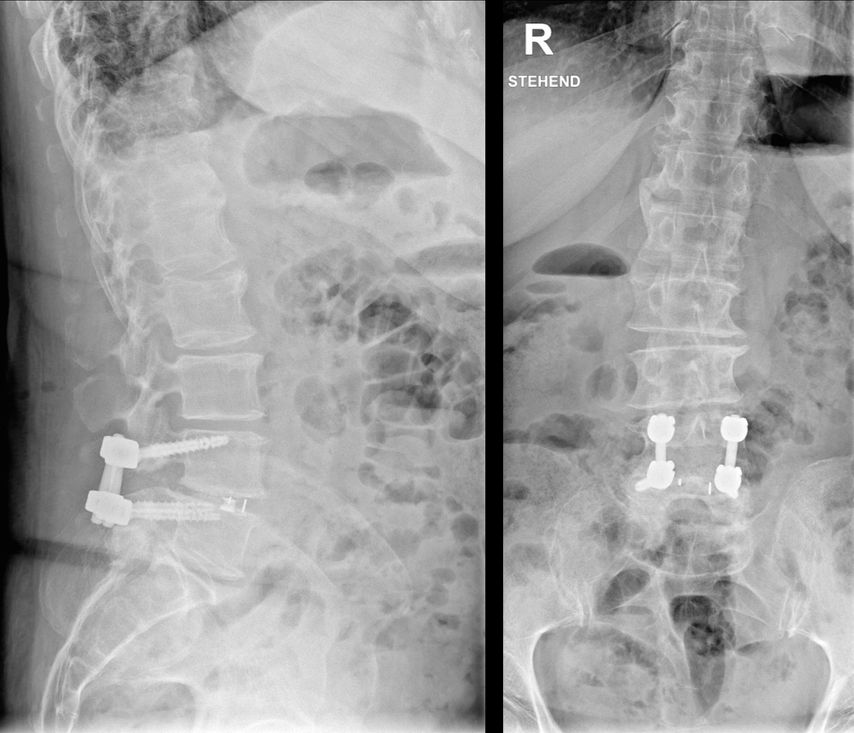

In der Brustwirbelsäule führen eine möglichst gerade Schraubentrajektorie und die Platzierung im kaudalen Abschnitt zur besten Fixierung.27 In der Lendenwirbelsäule wird die „cortical bone trajectory“ von mehreren Autor:innen propagiert, da sie durch die Zonen höchster Knochendichte verläuft. Von einem medialen Eintrittspunkt ausgehend werden die Schrauben divergierend und nach kranial aufsteigend gesetzt(Abb. 3).28 Biomechanisch erzielt sie den besten Halt, sie ist allerdings chirurgisch anspruchsvoller zu setzen.29, 30 Mit der Einführung von „patient-specific instruments“ und Navigation ist dies einfacher geworden.

Bei langstreckigen Osteosynthesen gelten bei osteoporotischen Patient:innen umso mehr die Grundregeln, nicht im Apex oder thorakolumbalen bzw. zervikothorakalen Übergang zu enden. Da wir an unserer Einrichtung vermehrt Insuffizienzfrakturen des Sakrums beobachtet haben, indizieren wir eine Abstützung auf das Ilium liberaler. Häufig werden Pedikelschrauben eingedreht, bis der Schraubenkopf knöchernen Kontakt hat. Dieses sogenannte „hubbing“ sollte vermieden werden, da dadurch der Querfortsatz, Lamina bzw. Gelenksfortsatz geschwächt und die Ausrissfestigkeit reduziert werden.31